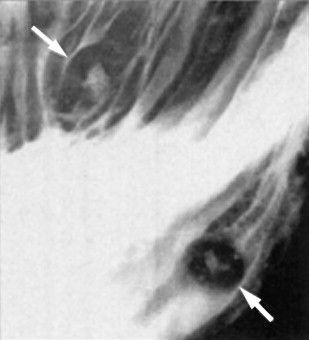

DDx for Smooth Oesophageal Strictures

DDx includes:

Inflammatory:

Neoplastic:

Others: